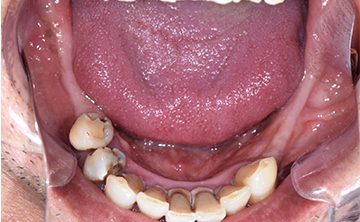

虫歯を放置して3年経って来院された患者さんです。噛めなくなったが主訴です。虫歯が進行しているのも確かですが、歯石も多く付着していますね。虫歯の中にオレンジのものが見えていますが、これは、根の治療後に詰める防腐剤ですね。

根の治療をすると歯に痛みを感じなくなるので、虫歯が進行しても痛みを感じずに歯冠崩壊を招きます。できるだけ歯の神経を取らない方が良いですが、虫歯が歯の神経に近く痛みが出る場合は、虫歯の歯の神経治療が必要になります。

非常に素晴らしい患者さんで、この後、しっかりと通って虫歯を全て治して、噛める状態にまで回復しました。